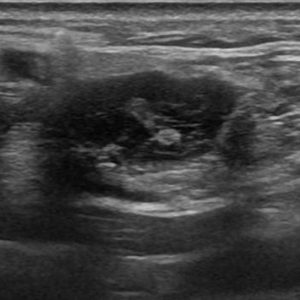

U tuyến nước bọt

Lượt xem: 102» 19-01-2021 -